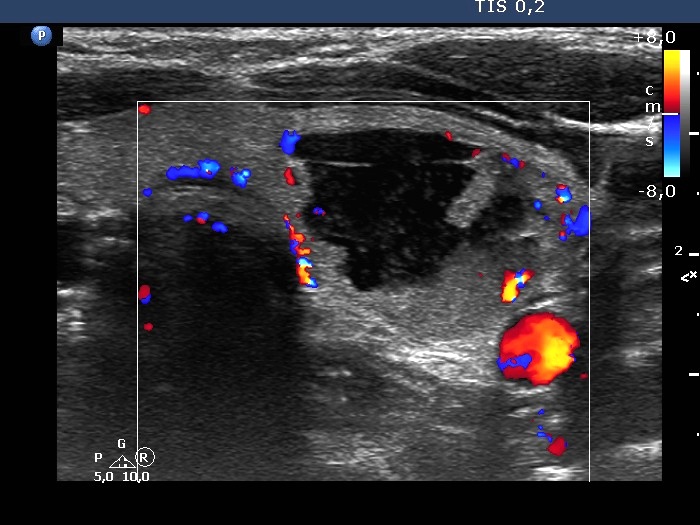

Right lobe, longitudinal scan

Left lobe, transverse scan, color Doppler mode. The lesion presents signs of perinodular blood flow.